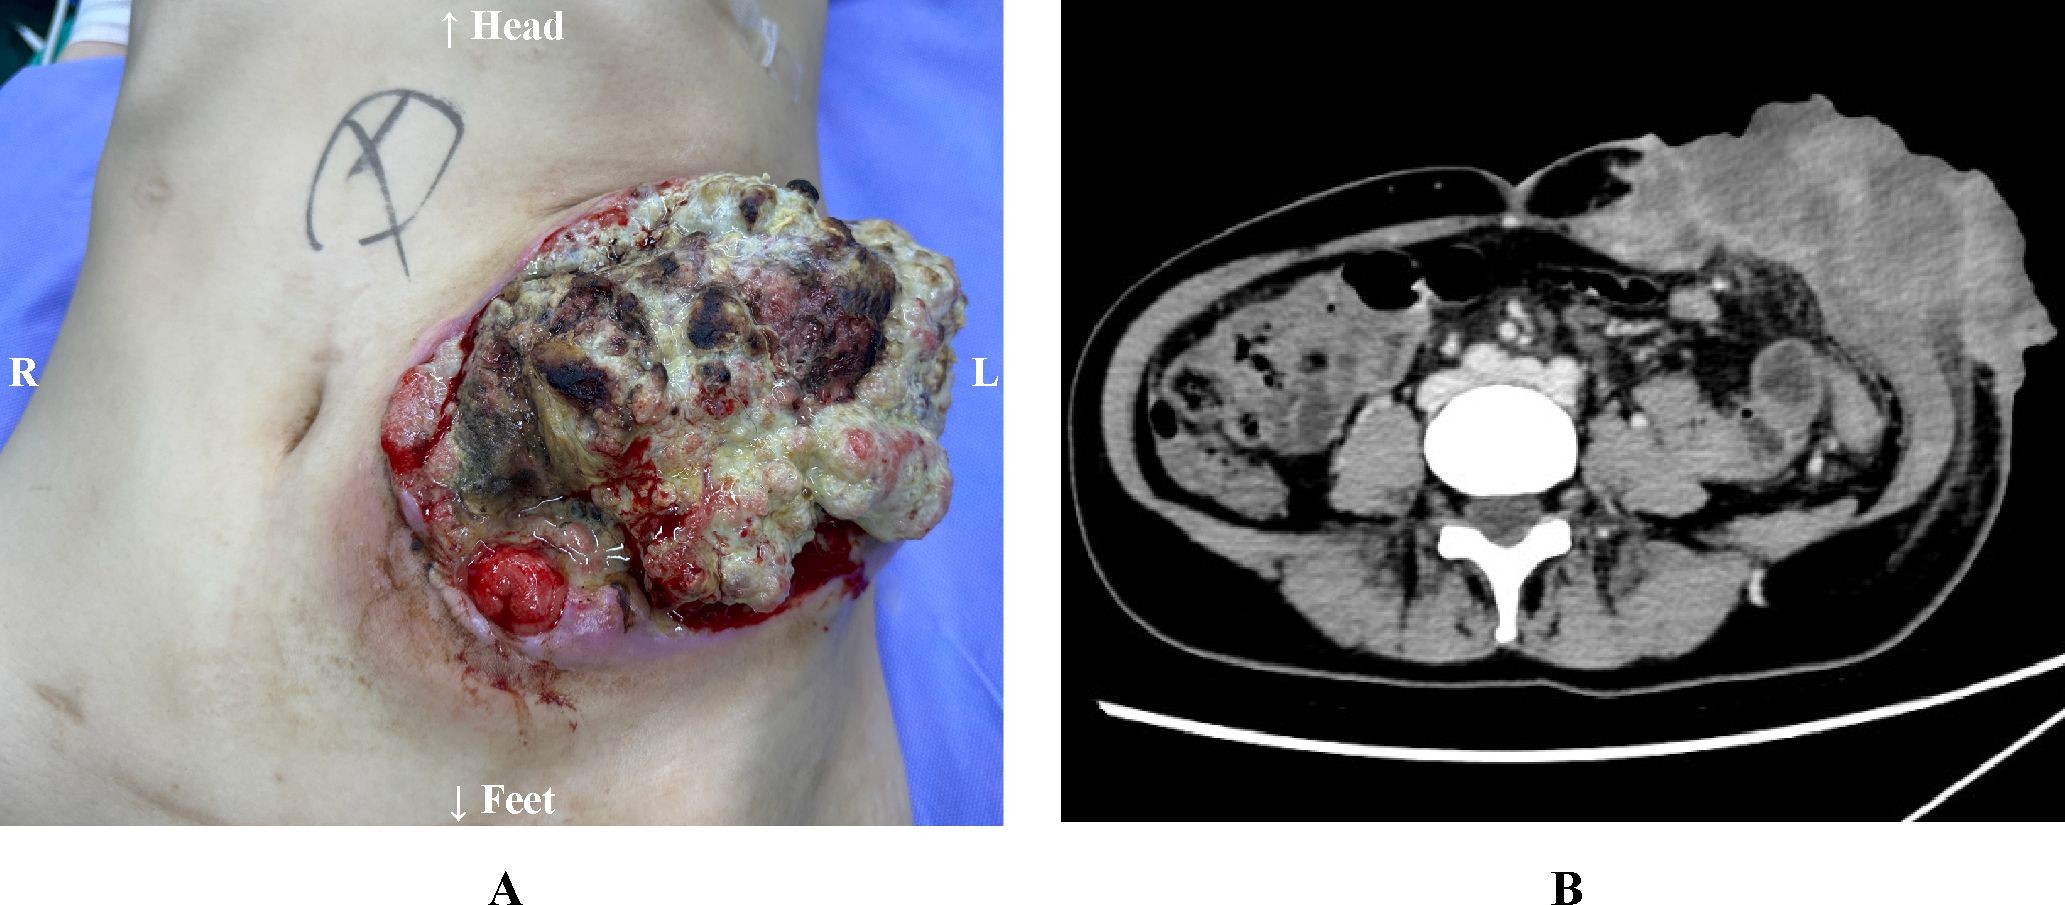

A 35-year-old woman presented with a local recurrence at the stoma site three months after Hartmann's procedure for sigmoid colon cancer. In the subsequent months, the tumor exhibited rapid progression, with direct invasion into the abdominal wall. Her clinical course was characterized by persistent pain, fever, foul odor, and defecation disorder. The substantial disease burden confined her to bed, leaving her unable to care for her two young children. Following a multidisciplinary team (MDT) evaluation, she was deemed a candidate for reoperative surgery. The procedure comprised en bloc resection of the recurrent tumor, followed by restoration of bowel continuity with a primary colorectal anastomosis and immediate abdominal wall reconstruction. The patient's postoperative recovery was uneventful, with a marked improvement in quality of life. This case highlights the critical role of flap-based reconstruction in managing complex abdominal wall defects.